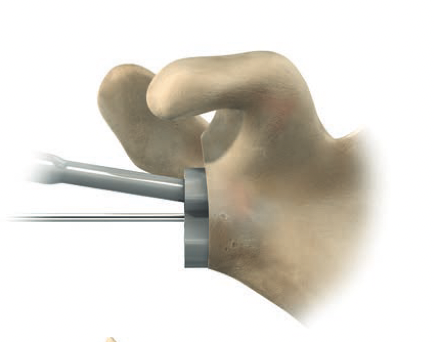

Glenoid baseplate

Remove all labrum and release capsule from glenoid

- identify inferior border of scapula

- ? release triceps from inferior border

- insert retractors to expose glenoid

Centering guide wire passed

Depuy Synthes Delta Xtend

Center of inferior circle of glenoid

- metaglene needs to be positioned low to prevent inferior impingement and dislocation

- wire needs to angle perpendicular or slightly inferior / avoid superior tilt

- should exit scapula anteriorly about 3cm medial to glenoid

- ensure inferior screw will be in inferior good bone

- ream cartilage to subchondral bone